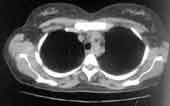

- Передние внутримаммарные л/узлы (Рис. 1), которые в норме не визуализируются, располагаются по ходу внутренней артерии молочной железы. Поражаются часто при раке молочной железы, реже при лимфогрануломатозе и лимфосаркоме.

Рис. 1. Передние внутримаммарные л/узлы.